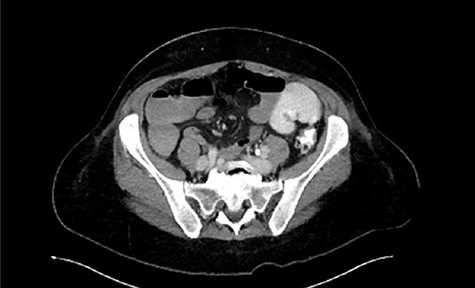

Immediate postoperative course was uneventful until postoperative day (POD)-5 when she experienced multiple watery stools, diffuse abdominal pain, fever (102.6F) and leukocytosis (23000/UL). Clostridium difficile infection was ruled out with a negative stool toxin assay. Her abdominal exam remained nonspecific until POD-6 when she had bilious emesis. A computed tomography (CT) scan revealed perforated diverticulitis with pelvic abscess and multiple colonic diverticulitis with an associated small bowel obstruction (SBO) (Images 1–4). No prior history of diverticulitis was reported.

Coronal image of pelvic abscess cavity. *: pelvic abscess cavity; White arrows: rim-enhancing pelvic abscess cavity; Blue arrows: collapsed sigmoid colon with multiple diverticuli.